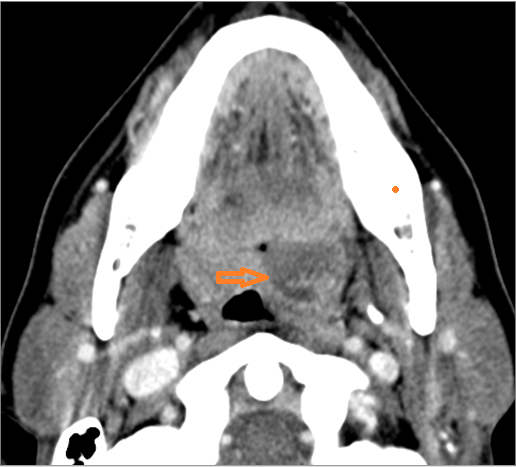

There is abscess at the periphery of the lymphoid tissue of the palatine tonsil within the potential peritonsillar space.